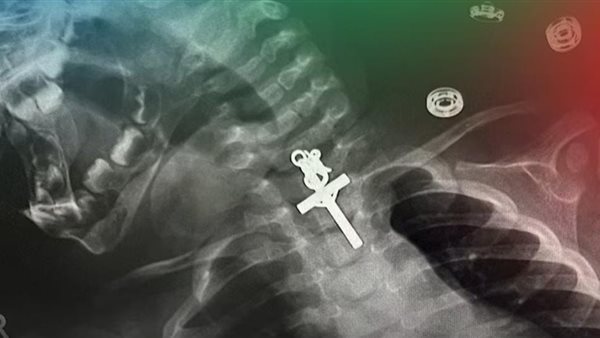

وأظهرت صور الأشعة السينية وجود الصليب في مريء الطفلة البالغ من العمر 10 أشهر.

ومن جانبه، قال لويس إستيفيس كابانيلاس، الطبيب المسؤول عن جراحة الأطفال: كان الإجراء معقدًا للغاية لأنه كان عبارة عن صليب وكان عالقًا في الثلث العلوي من المريء.

وأضاف كابانيلاس: وحتى عندما حاولنا إزالته في البداية، لم نتمكن من ذلك، لقد كان محشورًا، لذلك حاولنا عدة مرات حتى تمكنت من ذلك..وتم سحب الجسم الغريب إلى الخارج.